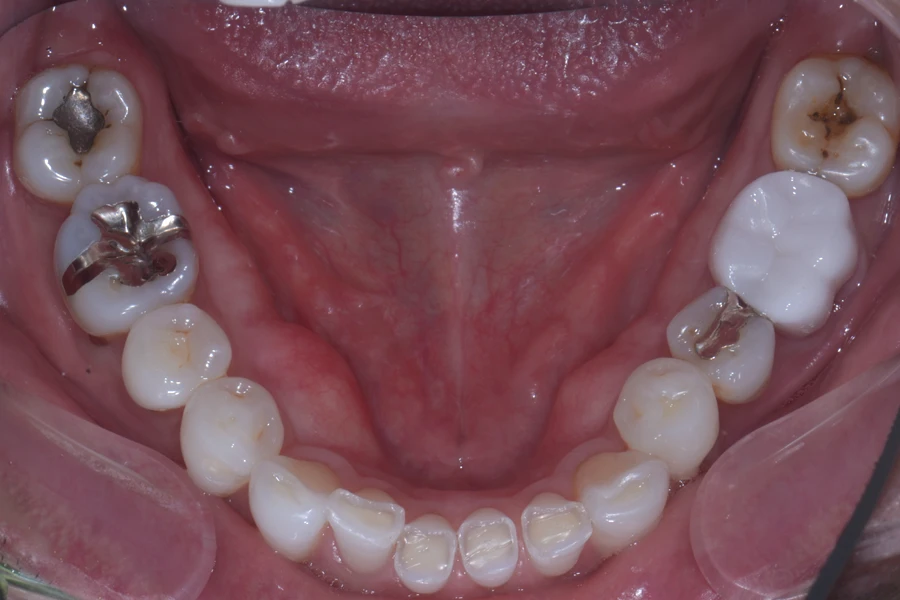

治療前